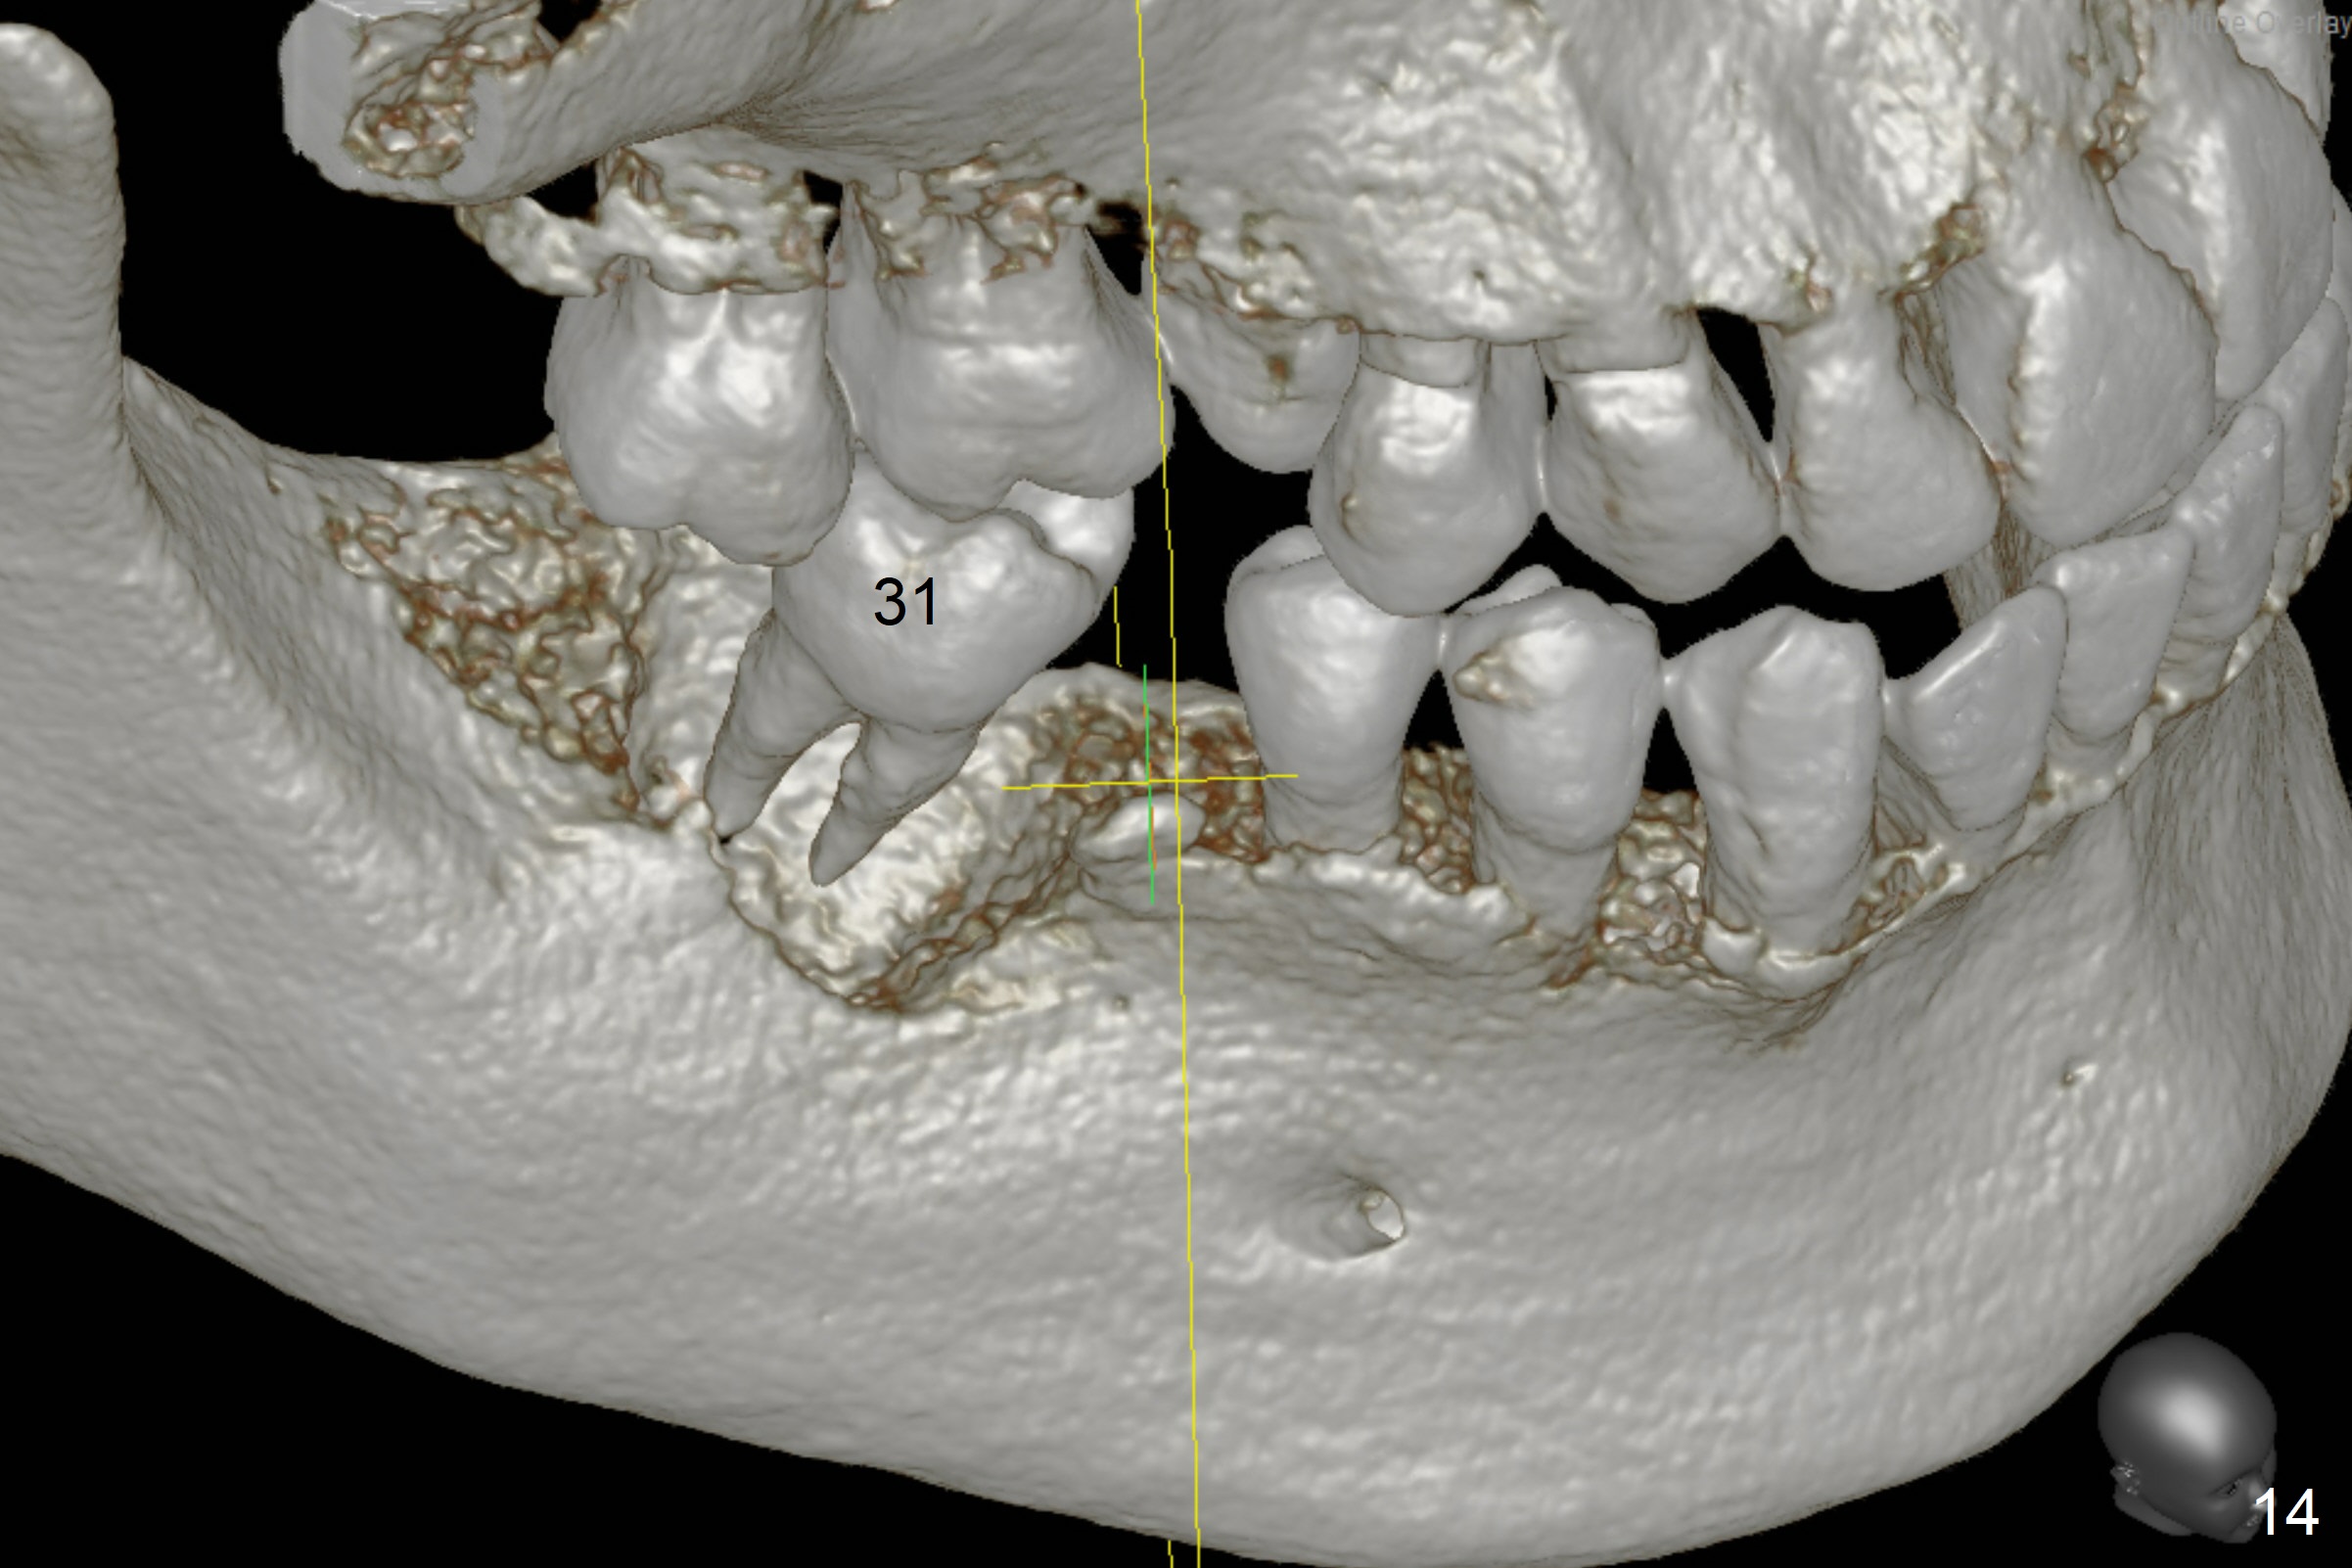

A 64-year-old man has discomfort with the lower left bridge and a loose tooth on the left (Fig.1). It appears that 4 implants are to be placed at #18,19,30 and 31. Since the tooth #4 and 13 are palatalized (Fig.2-4), the teeth #2 and 3 are mesialized (Fig.2 arrow). Besides, the ridge at #30 must be atrophic due to long termed edentulism. A small-diameter implant will be placed at #30 with premolar width (Fig.6-13), while the implant at #31 will be placed distal (arrow, as compared to Fig.2). To establish harmonious occlusion at provisional and final stages, the palatal slope of the mesiopalatal cusp of the tooth #2 will be adjusted (Fig.10).

Prepare 3 large pieces of gauze with the vasoconstrictor. If one of them is still too small for the socket, insert another piece of gauze without the vasoconstrictor for pressure hemostasis. Prepare PRF (x4) and Sinus Master Kit in case short stoppers are needed (Fig.12). CBCT taken immediately preop shows relatively wide ridge at #30 (Fig.14,16). The implant at #31 should be place in the distobuccal aspect of the socket (Fig.15,17): 2 mm drill with 7 mm stopper, 2.8 mm round drill at 5 mm (50 RPM) and 3.6 mm at 3 mm.